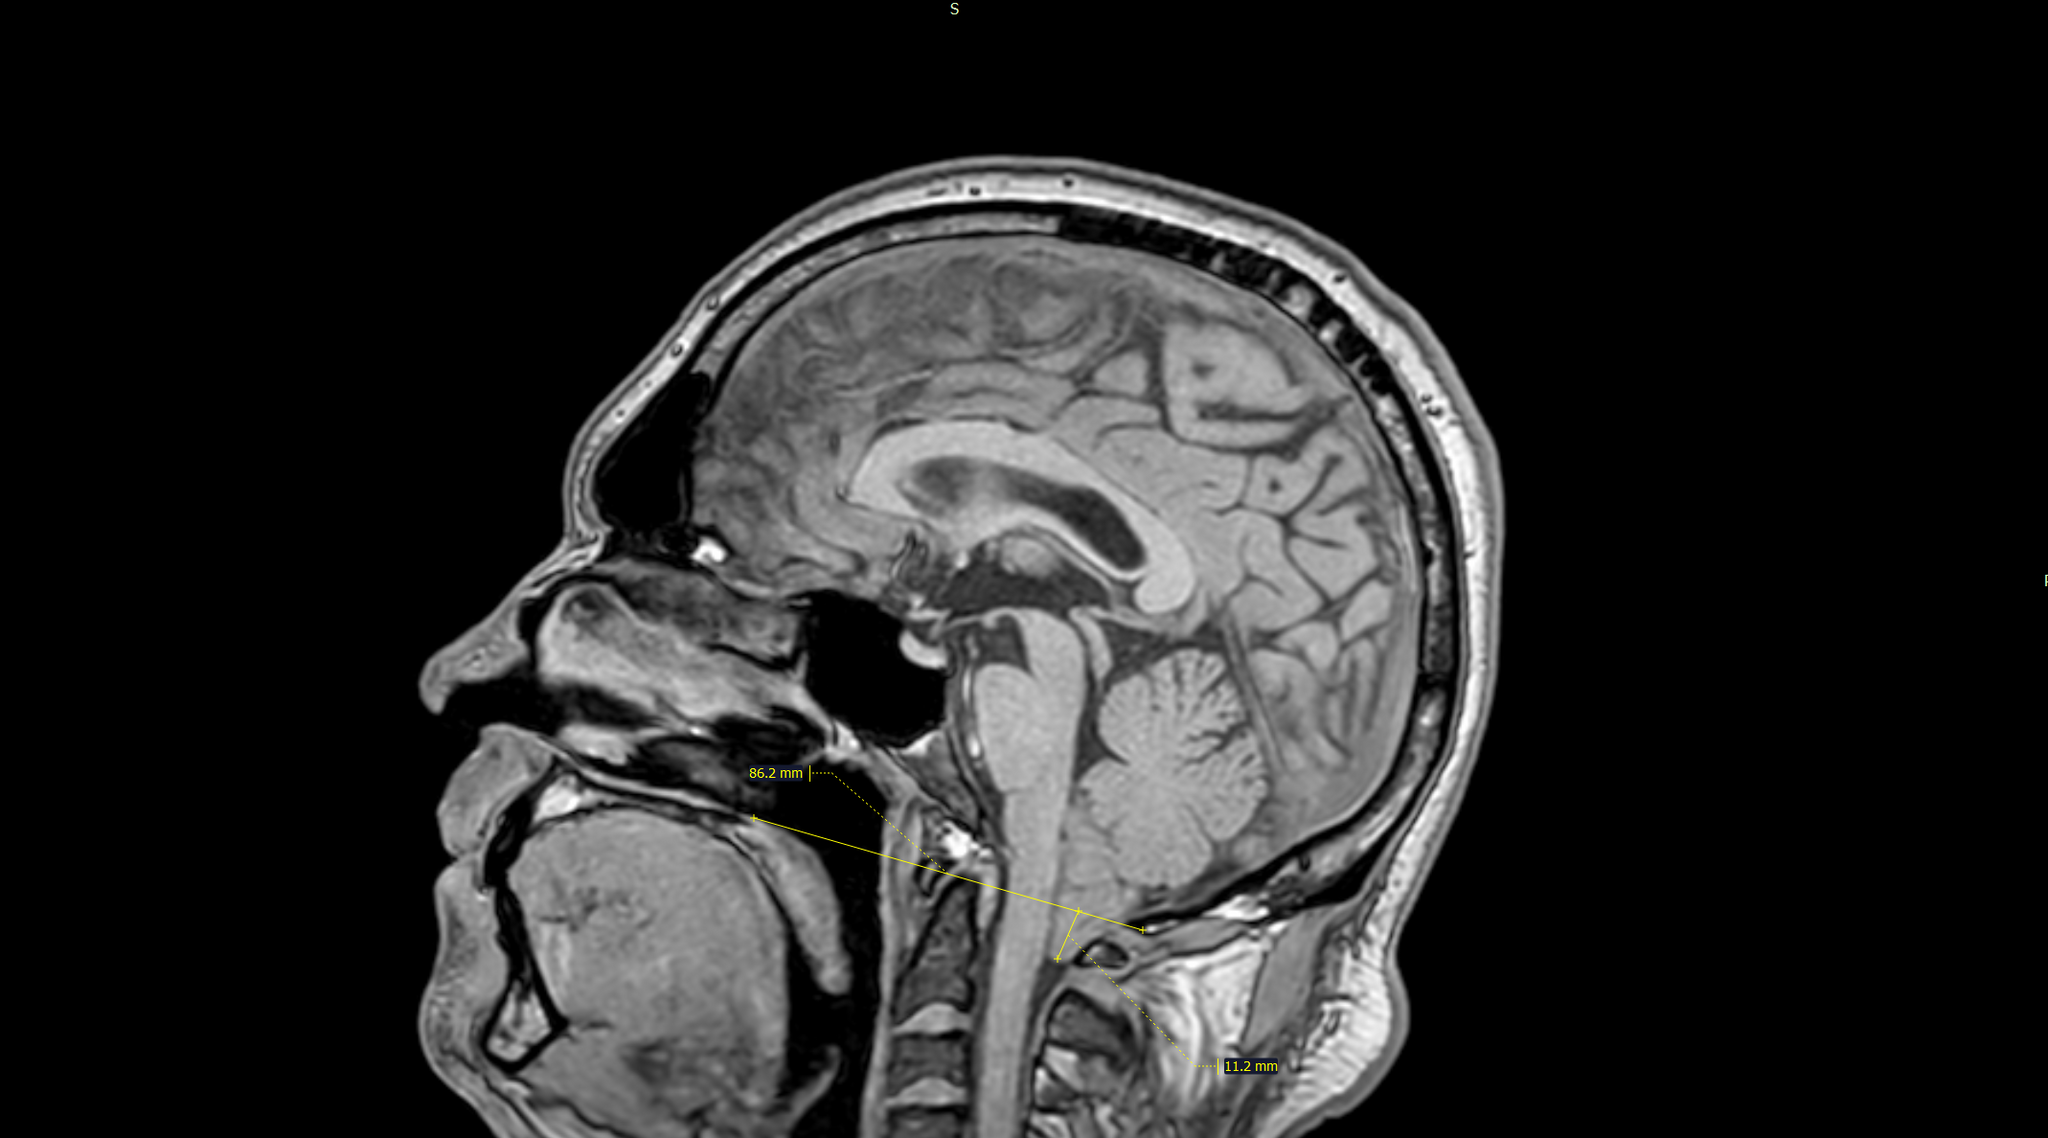

Смещение миндалин мозжечка ниже линии Чемберлена на 11мм.Заключение:Аномалия Арнольда-Киари 1 типа.

Смещение миндалин мозжечка ниже уровня большого затылочного отверстия (более чем на 5 мм).